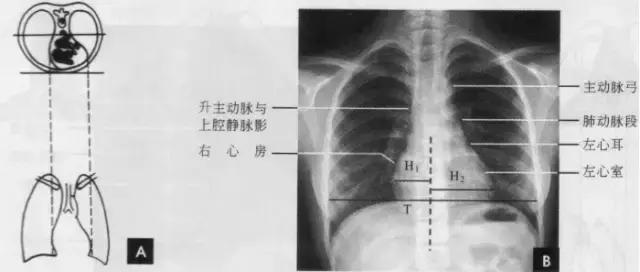

正常心影2/3位于中线左侧,1/3位于右侧,心尖指向左下,心底部朝向右后上方,形成斜的纵轴。后前位心脏大血管有左右两缘:心右缘分为两段,上段为升主动脉与上腔静脉的总合影,在幼年和青年人边缘主要为上腔静脉影向上延伸,在老年人常见纡曲延长的升主动脉影突出于上腔静脉边缘之外;心右缘下段为右心房所构成,有时在心瞩角内可见一向外下方倾斜的三角形影,为下腔静脉攻肝静脉影,深吸气时明显。心左缘分为三段,上段为主动脉弓;中段为肺动脉主干,但偶尔可为左稀动脉构成,称肺动脉段或心腰,此段较低平或稍突出:下段由左心室构成,左心室在下方形成心尖。左心室与肺动脉之间有长约10cm的一小段,由左心耳构成,正常时不能与左心室区分。透视下左心室与肺动脉段的搏动方向相反,两者的交点称相反搏动点,该点上下两侧心缘里“翘翘板”样运动,该点位置是衡量左右心室增大的一个重要标志。肥胖人左心膈角常有脂肪垫充填,为密度较低的软组织影。后前位能了解心胸及肺循环概况,正常人心(h1+h2)胸(t)比率不大于0.5(如下图)。